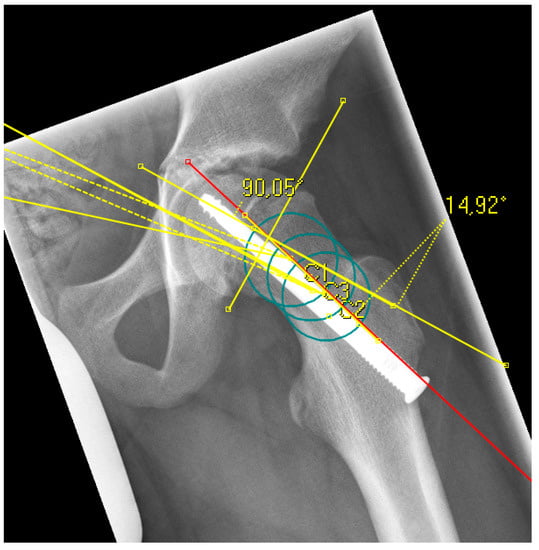

The radiological analysis directly after surgical fixation included the lateral center edge angle according to the sourcil method (LCEA) [22] and the acetabular angle (inclination) to evaluate the femoral coverage [23], especially regarding the presence of a hip dysplasia or coxa profunda, as well as the absolute slip angle according to Southwick [24,25]. The grading of the Southwick angle values is typically: mild (<30°), moderate (30–50°) and severe (>50°). Because the alpha angle is referenced to the femoral neck axis, this reference was the same for the posterior epiphyseal tilt to predict a FAI type cam over the time [26]. In contrast to the Southwick angle, which is determined as an angle between the slipped capital epiphysis and the femoral shaft axis, the posterior epiphyseal tilt was referenced also to the femoral neck axis like the alpha angle [27]. In addition, parameters for dysplasia resp. retroversion were evaluated, including the crossover sign (the anterior and posterior acetabular rims crossing on the pelvic a.p.) and the prominence of the ischial spine (PRISS; the ischial spine is projected in the lesser pelvic on the pelvic a.p.) [28]. In presence of a crossover sign and a positive PRISS a retroversion was assumed, whereas a dysplasia was defined with a LCEA <20 and an inclination >10°. All the described values were assessed again at the last time of the radiological follow-up, additionally the alpha angle [13]. In presence of a SCFE, the center of the femoral head is not always aligned to the axis of the femoral neck for measurement of the alpha angle and the posterior epiphyseal tilt. To avoid inaccuracy, the anatomical method according to Bouma et al. was used [29]. For this, the femoral neck axis was defined with three circles along the femoral neck, whichever fitted the bony neck best (Figure 1 and Figure 2).

Figure 2. Example of a radiograph with the measurement of the epiphyseal tilt based on the anatomical femoral neck axis (red line), which was determined with three circles (green) according to Bouma [29].